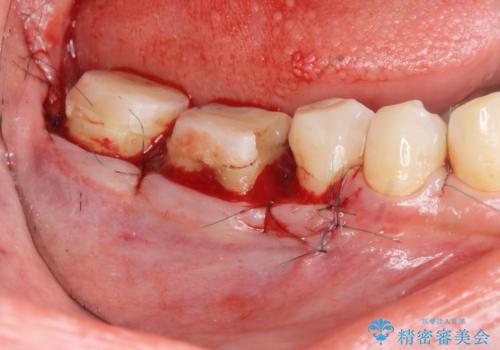

加えて、舌の邪魔になっている骨隆起や根尖病変といった問題を歯周外科・精密根管治療を行い、しっかりとスペースを確保したのちセラミッククラウンを作製していきます。

- 37.4万円(ジルコニアクラウン×2・仮歯×2・歯周外科手術)費用は治療当時の料金となります

- 外科手術のため、術後に出血、痛みや腫れ、違和感を伴います